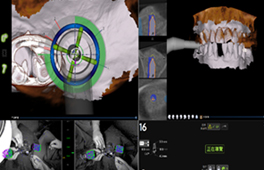

圖三、電腦模擬搭配導航植牙手術 (來源:楊濡瑄醫師)

(左)手術前用電腦模擬植牙位置。(右)手術中利用導航系統精準植牙在計畫位置。